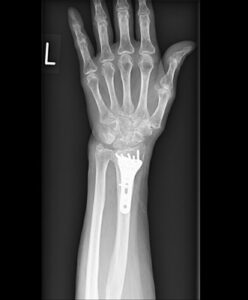

整形外科